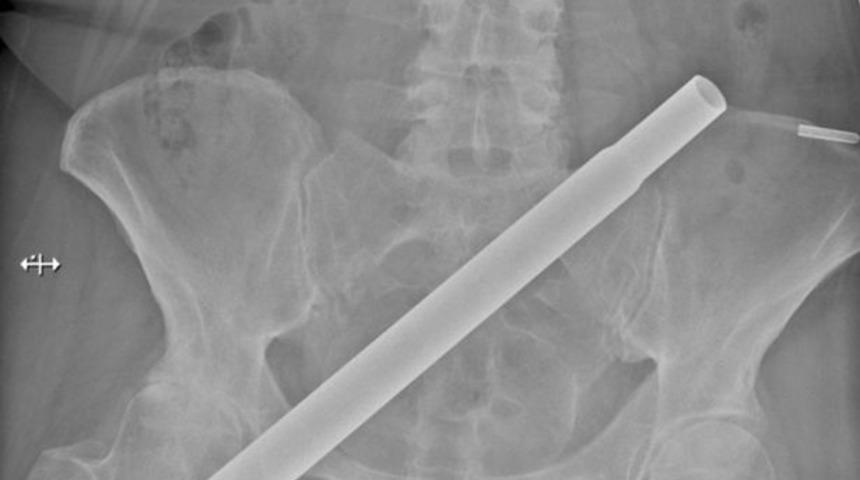

Daisy Hill Hastanesi'ndeki çalışan Dimitrios Angelou ve meslektaşlarının travmatik yaralamalar söz konusu olduğunda hastanelerinin hızlı hareket etmesinin önemine değindikleri makalenin konusunu 54 yaşındaki bir kadının yaşadığı tuhaf kaza oluşturdu. Doktorlar tarafından yapılan açıklamada, “Hastamız bir merdivenden yapay Noel ağacının metal direğinin üzerine düşen bir kadın. Ağacın gövdesi sağ kalçasından pelvisine doğru girdi. Korkunç yaralanmaya rağman şans eseri yaşamı tehdit eden bir kanama olmadı” ifadelerini kullandı.

Olay yerine çağrılan itfaiye ekiplerinin metal direği kesmesinin tam 1 buçuk saat sürdüğü belirtildi. Ameliyat için yerel bir travma merkezine nakledilen kadın hasta anında ameliyata alındı. Durumunun iyi olduğu belirtilen kadın kısa sürede iyileşti ve normal hayatına geri dönebilmeyi başardı.